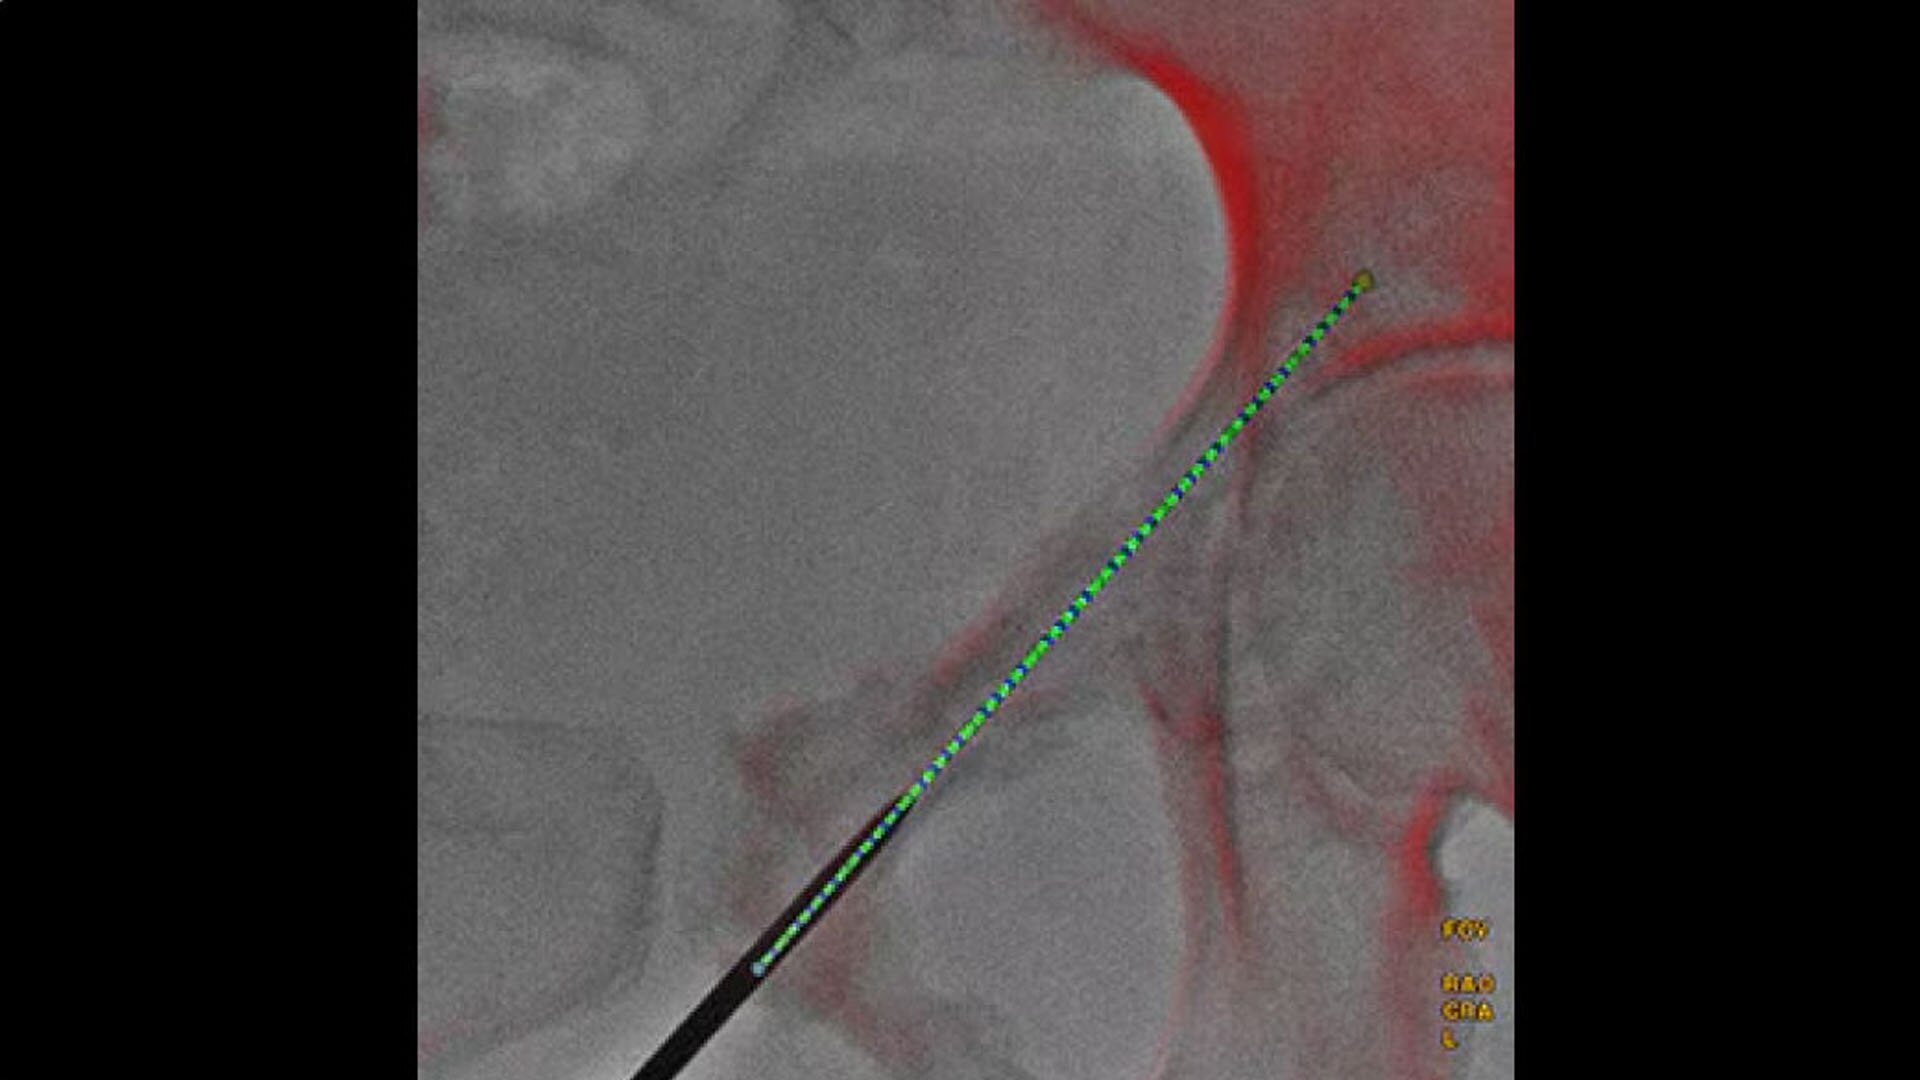

Real-time visualization

Provide real-time visualization of needle positions in the 3D space

Needle ASSIST for needle positions in the 3D space

Performing needle procedures in the interventional suite frees up your CT system and provides exceptional access to the patient.